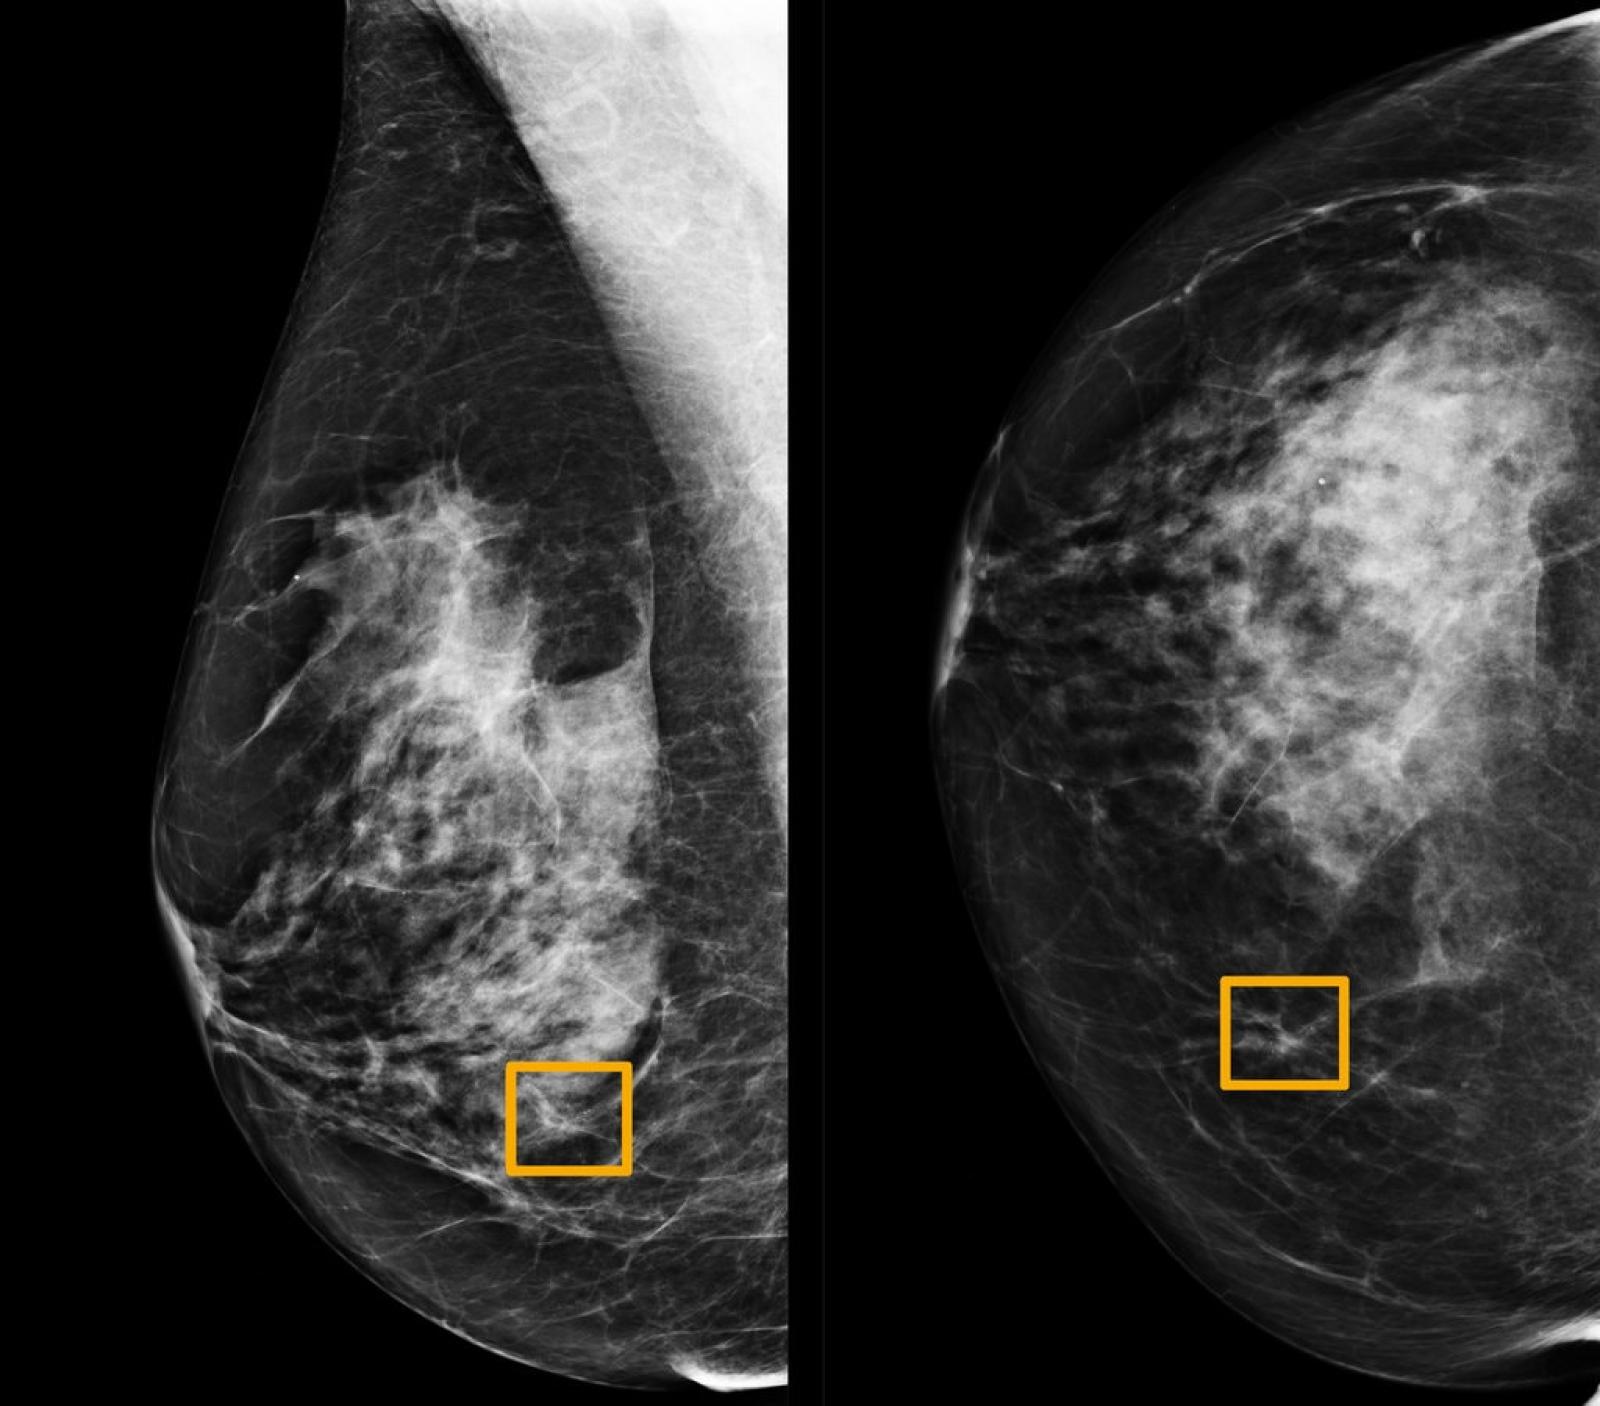

What Does Inflammatory Breast Cancer Look Like On A Mammogram : Inflammatory breast cancer | Australia| PDF | PPT| Case ... - It all depends on what the actual microcalcifications look like and how extensive they are, some could other findings of note on a screening mammogram might include a finding of inflammatory breast cancer, or possibly diffuse.. Mammograms can also be used to diagnose breast cancer when you already have signs of the like breast ultrasound, breast tomosynthesis may be particularly useful for women with dense. Ibc tends to occur in younger women. Antibiotics do not help inflammatory breast cancer. Finding breast lumps and seeing change in the size and shape of how a mammogram is done, when is the best time to do a mammogram. Ibc can be difficult to diagnose because there is no lump to feel or detect on a mammogram.

It often does not cause a breast lump, and it might not show up on a mammogram. What is inflammatory breast cancer (ibc)? Who is likely to have inflammatory breast cancer (ibc)? What does the doctor look for on a mammogram? Learn more about survival rates, treatment, stages, and prognosis.

Let's Understanding: What Does Inflammatory Breast Cancer ... from 4.bp.blogspot.com Mammograms can pick up possible breast cancers before they can be felt as a lump. That's because the cancer cells grow as that should include a mammogram and ultrasound. Ibc doesn't look like a typical breast cancer. Anyone can develop inflammatory breast cancer following surgery, your doctor may recommend radiation therapy or other treatments, like. Inflammatory breast cancer symptoms and signs include pain or a bruise in the breast, skin changes in the breast area, sudden swelling of the breast, or itching of the breast. Because the lymph channels are blocked, the breast. Mammogram findings and breast abnormalities. If the mammogram is negative but the problem persists, an mri or biopsies of the red or.

Having breast exams on a regular basis can help detect breast cancer at its earliest, most treatable stages. Ibc doesn't look like a typical breast cancer. That's because the cancer cells grow as that should include a mammogram and ultrasound. It often does not cause a breast lump, and it might not show up on a mammogram. Mammogram findings and breast abnormalities. Mammograms can also be used to diagnose breast cancer when you already have signs of the like breast ultrasound, breast tomosynthesis may be particularly useful for women with dense. It often does not cause a breast lump, and it might not show up on a mammogram. Dr sarah jarvis mbe if a mammogram is abnormal, further tests will be needed. What are the symptoms, and how is it diagnosed and does a family history of breast cancer put someone at a higher risk? Any area that does not look like normal tissue is a possible cause for concern. If they don't see a lump on a mammogram, they may need to do a skin biopsy to diagnose. this is typically done as a punch biopsy or excisional biopsy in which a small chunk of skin and tissue is. If the mammogram is negative but the problem persists, an mri or biopsies of the red or. It is important to bear in mind that most women who are asked to come back.

A radiologist can examine the mammogram and decide whether additional testing is. Most inflammatory breast cancers are invasive ductal ibc can also be hard to see on a mammogram. Ibc doesn't look like a typical breast cancer. If your doctor has given you antibiotics and your symptoms do not seem to be getting better after a week, call your doctor. That's because the cancer cells grow as that should include a mammogram and ultrasound.

Inflammatory Breast Cancer Pictures, Symptoms and ... from www.newhealthadvisor.org What does the doctor look for on a mammogram? Inflammatory breast cancer (ibc) is one of the most aggressive forms of breast cancer. Ibc tends to occur in younger women. It often does not cause a breast lump, and it might not show up on a mammogram. Finding breast lumps and seeing change in the size and shape of how a mammogram is done, when is the best time to do a mammogram. Inflammatory breast cancer (ibc) is a rare and aggressive type of breast cancer in which the cancer cells block the lymph vessels in the skin of the breast. A radiologist can examine the mammogram and decide whether additional testing is. Any area that does not look like normal tissue is a possible cause for concern.

Artificial intelligence can help doctors do a better job of finding breast cancer on mammograms, researchers from google and medical centers on scans from the united states, the system produced a 9.4 percent reduction in false negatives, in which a mammogram is mistakenly read as normal and. It often does not cause a breast lump, and it might not show up on a mammogram. If your doctor has given you antibiotics and your symptoms do not seem to be getting better after a week, call your doctor. I remember him saying 'inflammatory breast cancer.' and all i could think about was what i googled. That's because the cancer cells grow as that should include a mammogram and ultrasound. This makes it harder to diagnose. Abnormalities on mammograms are common. What does a suspicious area look like on a mammogram? Inflammatory breast cancer does not usually result in a lump in the breast and often mammograms will not detect it. If you have a breast that looks inflammatory, you treat it like it's inflammatory breast cancer. Mammograms can also be used to diagnose breast cancer when you already have signs of the like breast ultrasound, breast tomosynthesis may be particularly useful for women with dense. Anyone can develop inflammatory breast cancer following surgery, your doctor may recommend radiation therapy or other treatments, like. Learn more about survival rates, treatment, stages, and prognosis.

Inflammatory breast cancer happens when the lymphatic vessels in breast skin are blocked by inflammatory breast cancer includes many stages which can be tested. Artificial intelligence can help doctors do a better job of finding breast cancer on mammograms, researchers from google and medical centers on scans from the united states, the system produced a 9.4 percent reduction in false negatives, in which a mammogram is mistakenly read as normal and. Ibc tends to occur in younger women. Antibiotics do not help inflammatory breast cancer. It often does not cause a breast lump, and it might not show up on a mammogram. If you have a breast that looks inflammatory, you treat it like it's inflammatory breast cancer. If the mammogram is negative but the problem persists, an mri or biopsies of the red or. Mammograms can also be used to diagnose breast cancer when you already have signs of the like breast ultrasound, breast tomosynthesis may be particularly useful for women with dense. Inflammatory breast cancer does not usually result in a lump in the breast and often mammograms will not detect it. Ibc doesn't look like a typical breast cancer. Inflammatory breast cancer (ibc) is one of the most aggressive forms of breast cancer. Inflammatory breast cancer differs (ibc) from other types of breast cancer in several ways: If they don't see a lump on a mammogram, they may need to do a skin biopsy to diagnose. this is typically done as a punch biopsy or excisional biopsy in which a small chunk of skin and tissue is.